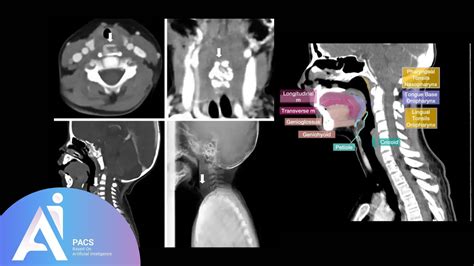

A CT scan of neck, often referred to as computed tomography, is a sophisticated diagnostic imaging procedure that utilizes X-rays combined with computer processing to create detailed, cross-sectional images of the structures within your neck. Whether your physician is investigating a persistent lump, evaluating unexplained pain, or monitoring a known condition, this imaging tool provides a level of clarity that standard X-rays cannot match. By capturing slices of the neck’s anatomy—including the thyroid gland, lymph nodes, blood vessels, and spinal structures—doctors can pinpoint abnormalities with remarkable precision, making it an essential component in modern diagnostic medicine.

The technology behind a CT scan of neck is fascinating. The patient lies on a motorized table that slides into a large, doughnut-shaped scanner. As you move through the scanner, an X-ray tube rotates around you, sending thin beams of radiation through your body. Detectors on the opposite side of the scanner record these beams, and the computer processes this information to create detailed, 3D-like images of the internal structures.

In many cases, the radiologist may decide that a contrast dye is necessary to enhance the visibility of specific tissues, blood vessels, or abnormalities. This contrast material, usually iodine-based, is typically injected into an intravenous (IV) line in your arm before the scan begins.